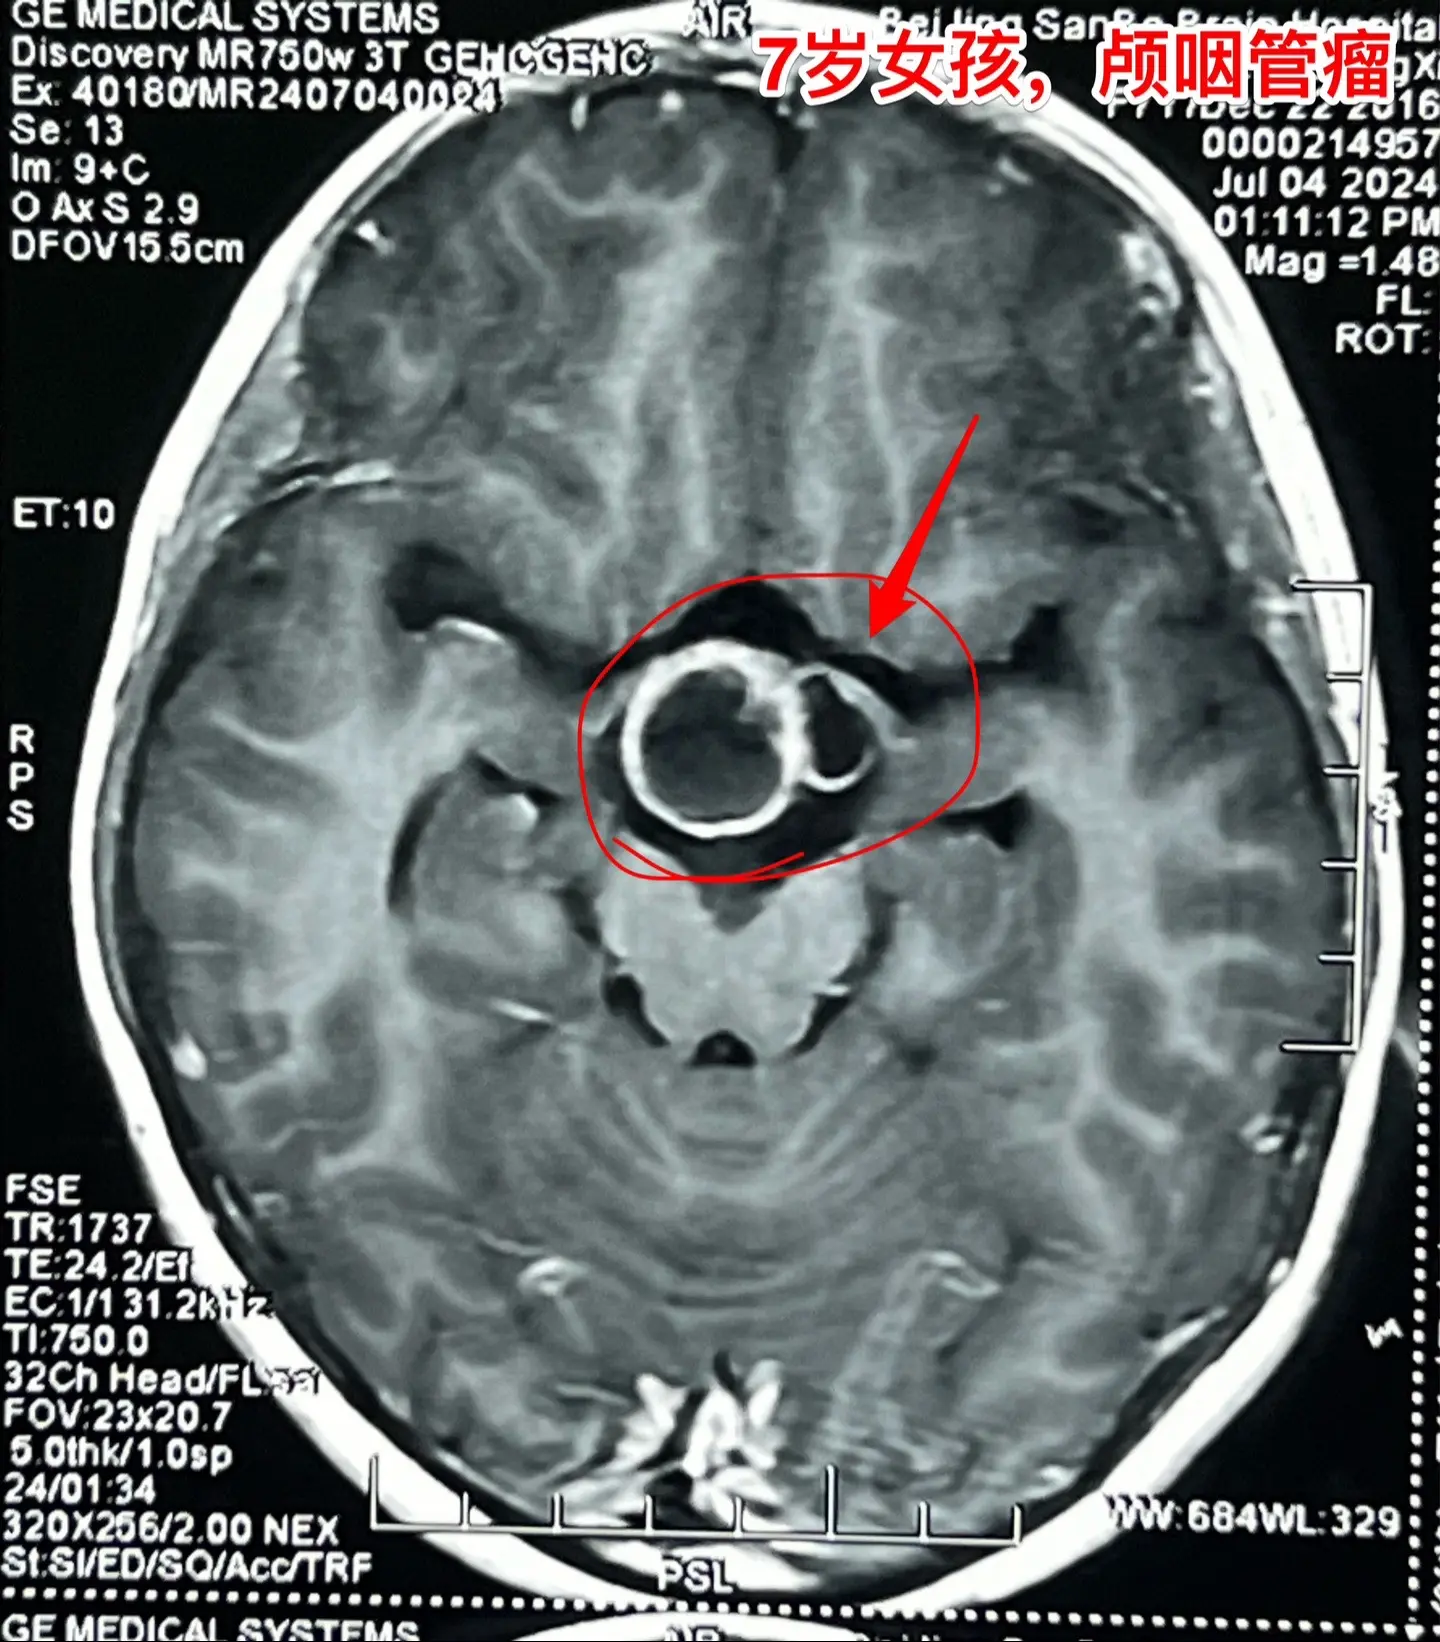

头痛、恶心、呕吐,是颅内高压症状!7岁江西上饶的小女孩,一个月前感头痛、恶心、呕吐。这是颅内高压的症状。他们到就近的医院就诊,作头部CT和磁共振,发现了颅咽管瘤,这个颅咽管瘤造成了梗阻性脑积水,颅内高压,所以小孩子出现头痛、呕吐症状。 根据头CT可以看见肿瘤内有钙化,可以确诊是典型的造釉细胞性颅咽管瘤。这样的肿瘤造成的脑积水,一般在切除肿瘤后就可以自愈,不需要专门作脑积水的手术。 2024年7月12日作了手术,肿瘤得到完全切除。 目前小孩子身体状况很好,快要出院了。